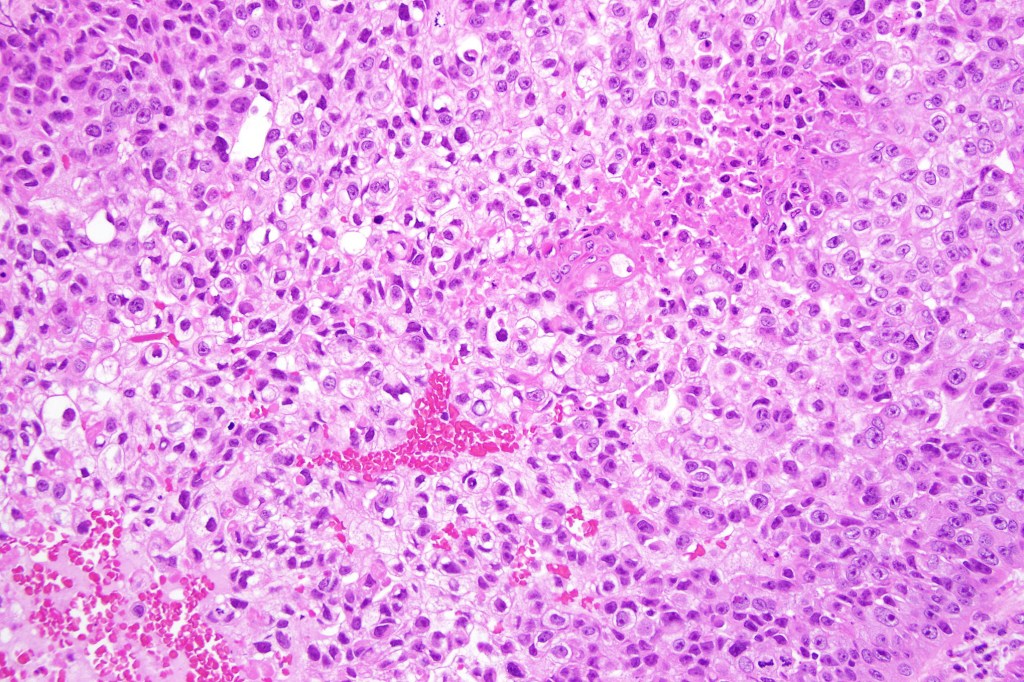

•Clear cell change results from cytoplasmic glycogen accumulation

•Can be focal or involve most of the tumor

If obvious squamous differentiation is not apparent, then metastatic clear cell carcinoma is an important differential diagnosis. Clear cell change may also be seen in a wide range of tumors including basal cell carcinoma, trichilemmal carcinoma, clear cell hidradenocarcinoma, porocarcinoma & melanoma. These are all discussed in respective blogs.